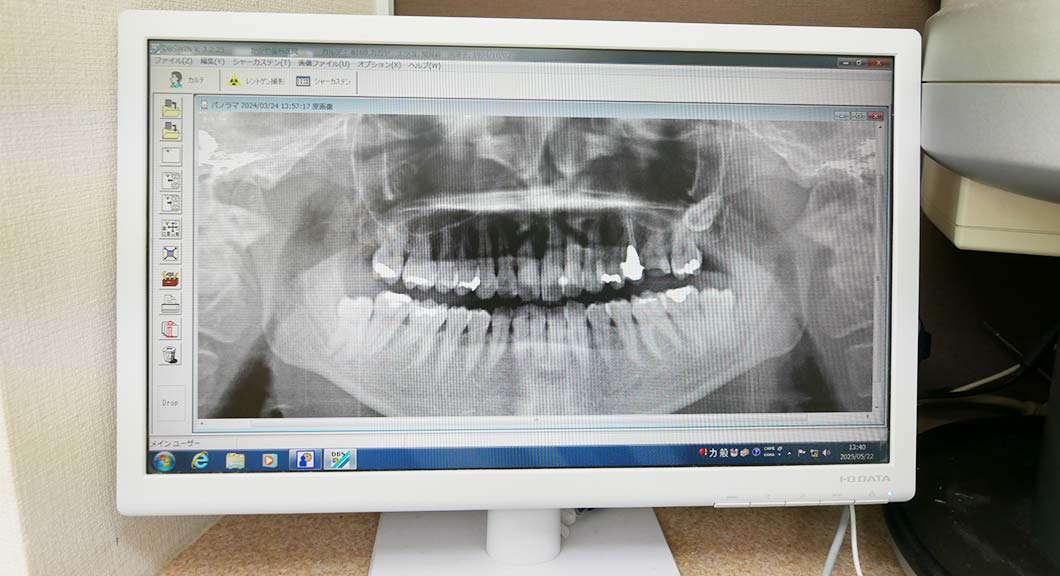

診療内容むし歯/歯周病/入れ歯/小児歯科/予防・クリーニング/インプラント/ホワイトニング/審美治療/マウスピース製作/歯科口腔外科/マタニティ歯科診療